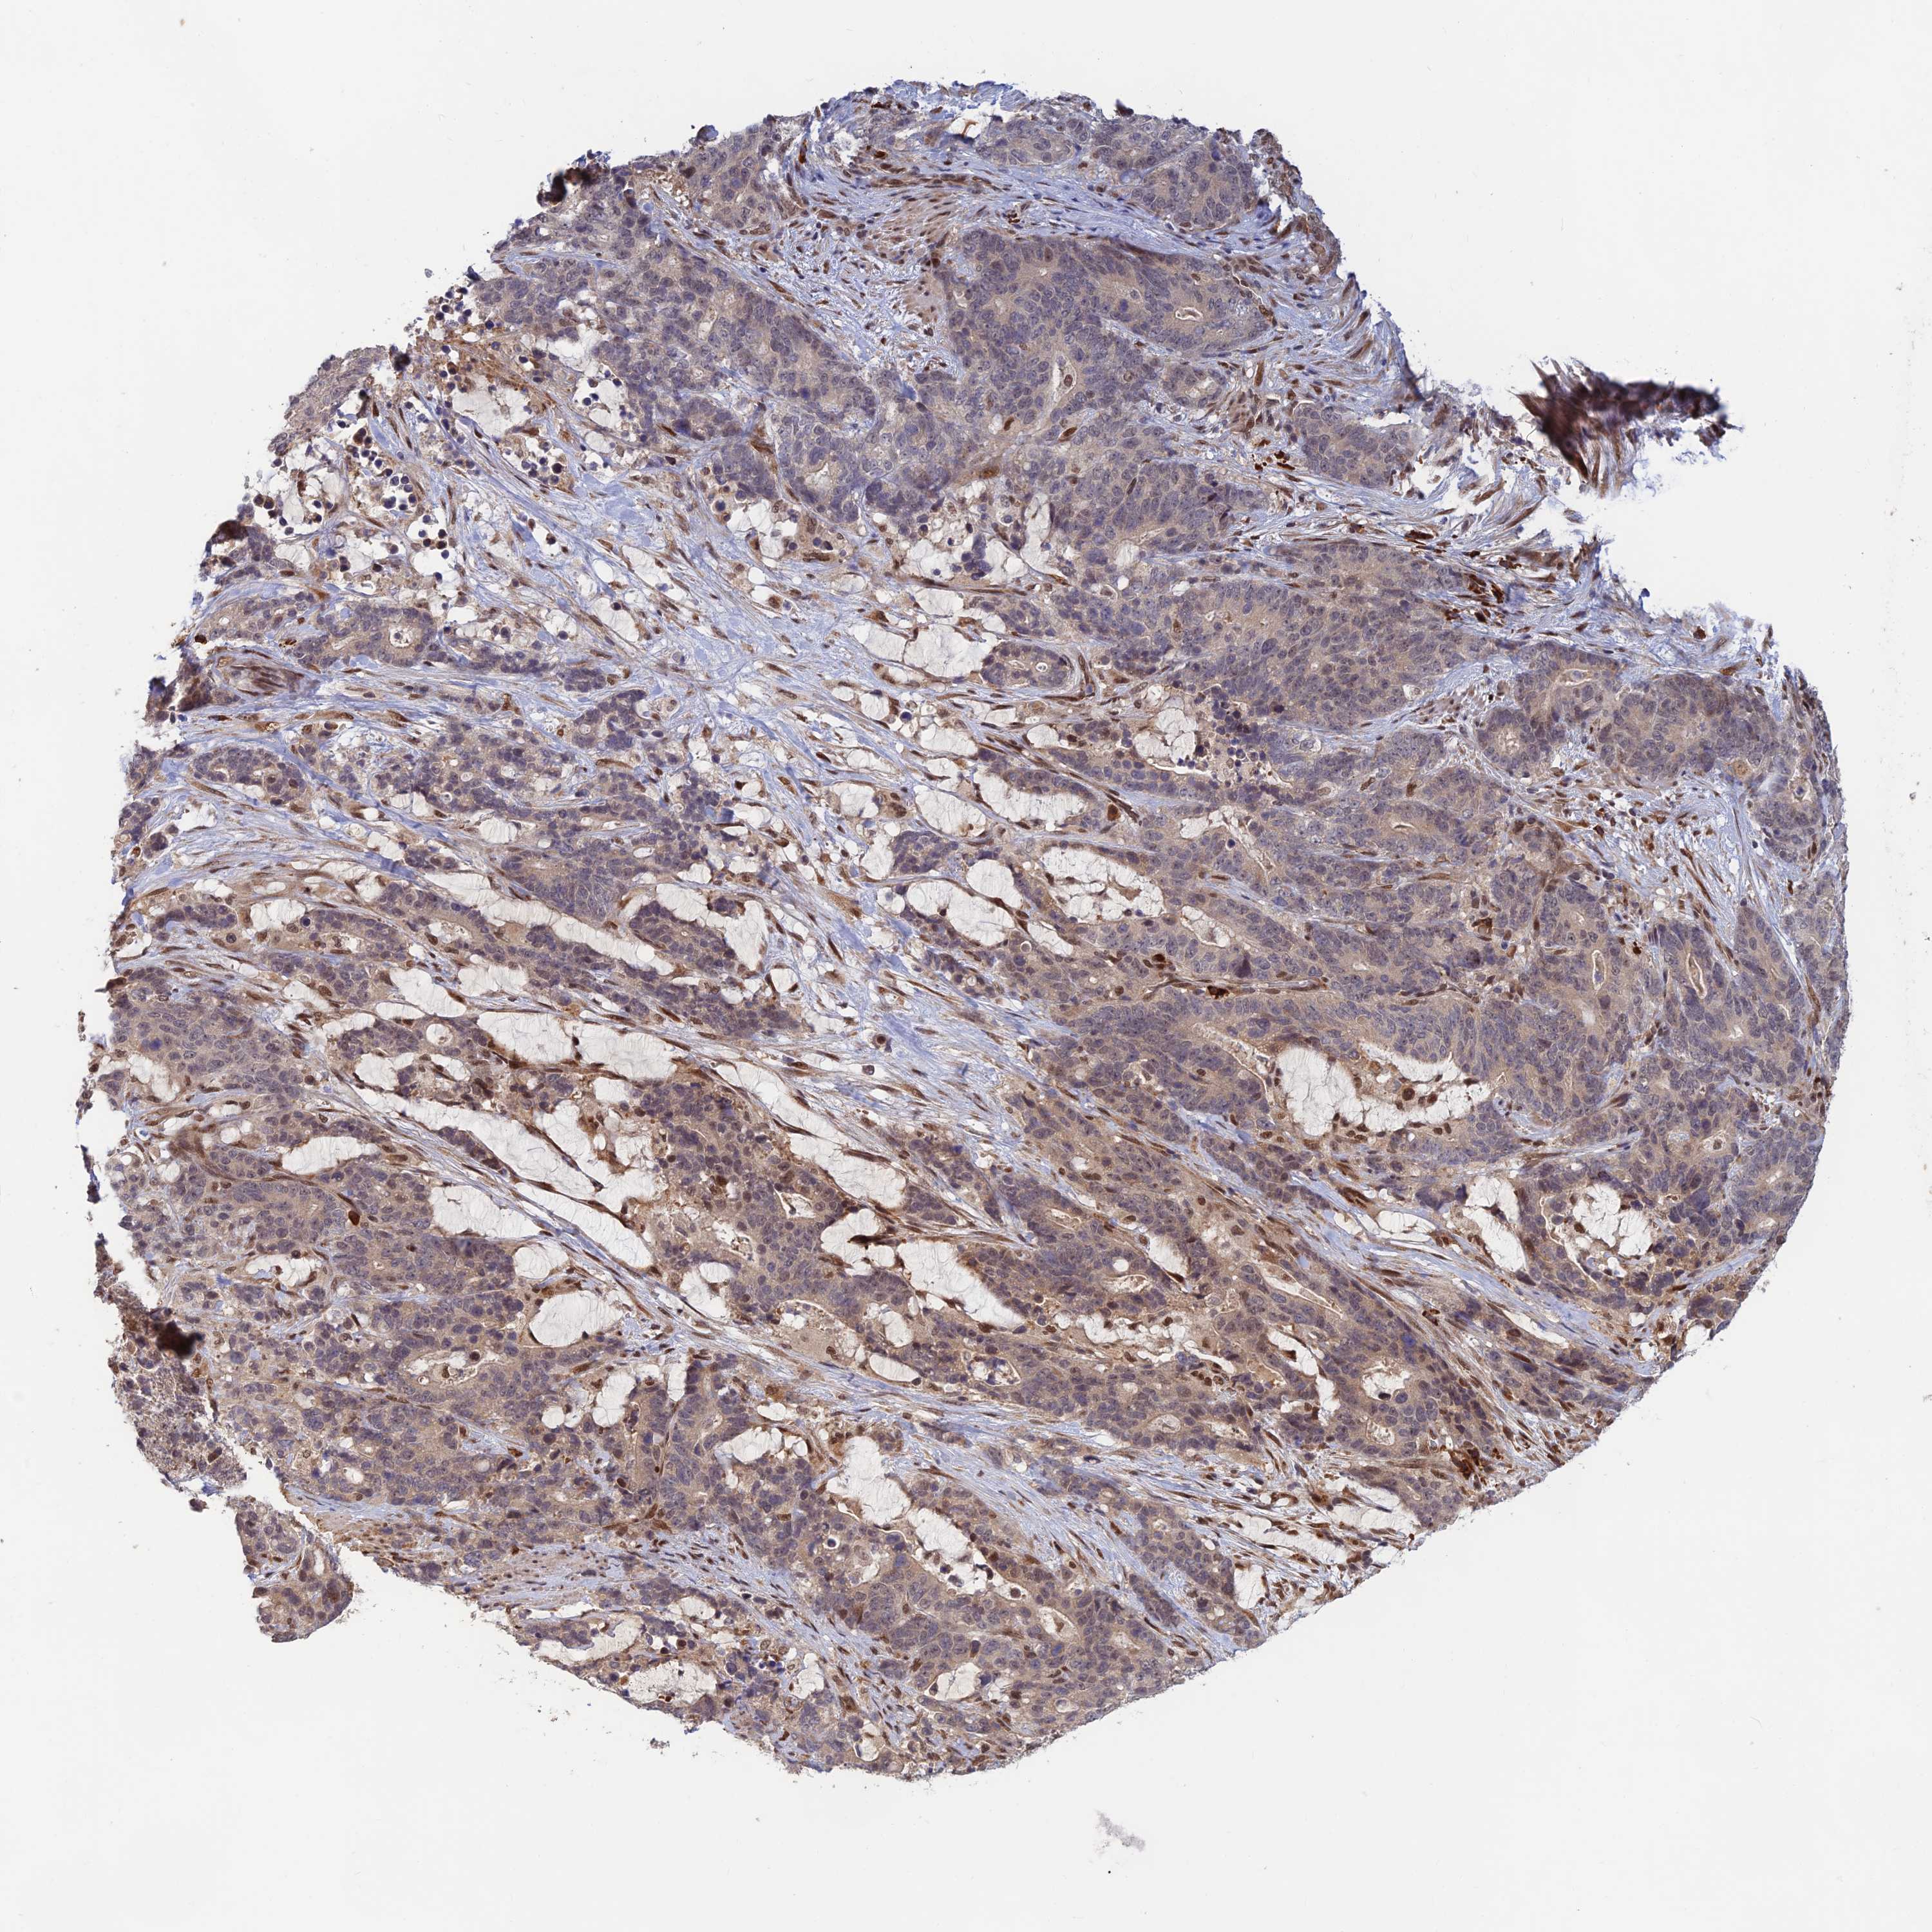

STOMACH CANCER - Protein expressioni

A mouse-over function shows sample information and annotation data. Click on an image to view it in a full screen mode. Samples can be filtered based on level of antibody staining by selecting one or several of the following categories: high, medium, low and not detected. The assay and annotation is described here.

Note that samples used for immunohistochemistry by the Human Protein Atlas do not correspond to samples in the TCGA dataset.

Antibody stainingi

Antibody staining in the annotated cell types in the current human tissue is reported as not detected, low, medium, or high, based on conventional immunohistochemistry profiling in selected tissues. This score is based on the combination of the staining intensity and fraction of stained cells.

Each image is clickable and will lead to virtual microscopy that enables deeper exploration of all samples and also displays staining intensity scores, fraction scores and subcellular localization as well as patient and tissue information for each sample.

Antibody HPA044123

Staining

High

Medium

Low

Not detected

Intensity

Strong

Moderate

Weak

Negative

Quantity

>75%

75%-25%

<25%

None

Location

Nuclear

Cytoplasmic/membranous

Cytoplasmic/membranous,nuclear

Adenocarcinoma, NOS